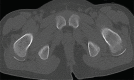

Myossitis ossificans (MO) is a benign disorder characterized by heterotopic bone formation in skeletal muscle. It is divided in three types, fibrodysplasia ossificans progressive (FOP), myositis ossificans circumscripta or traumatica (MOT) and myositis ossificans without a history of trauma (non traumatic or pseudomalignant MO). Myositis ossificans is extremely rare in children younger than 10 years. We present the clinical and radiological findings of two 5-year-old children with pseudomalignant MO due to prolonged immobilization. Plain x-ray films and CT scan with their characteristic findings of mature bone in the periphery of the lesion with smooth contour and well separated from the bone, enabled us to diagnose the lesion. To the best of our knowledge, no such cases have been reported in the literature.